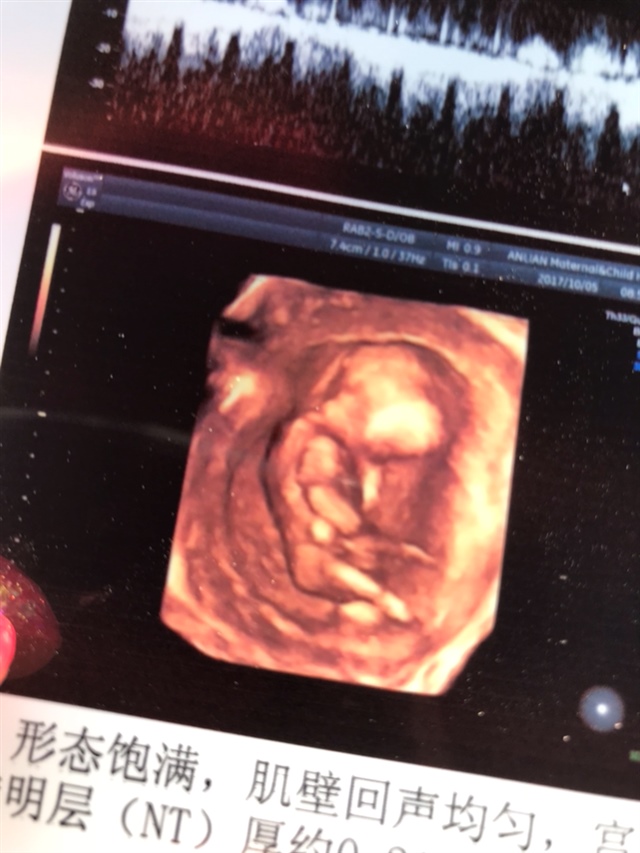

孕9周+5天

女孩

大琦🐳[帖主]: 怎么看的女孩呢,好多人都说像男孩